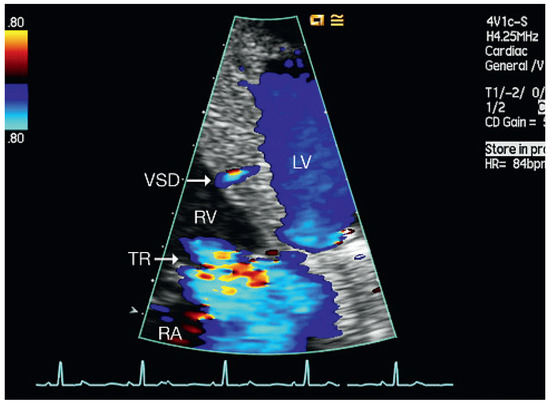

Muscular Ventricular Septal Defect After Mitral and Aortic Valve Replacement

by Augusto Aragão, Dorothea Vogel and Christoph Schmidt

Cardiovasc. Med. 2010, 13(5), 167; https://doi.org/10.4414/cvm.2010.01500 - 26 May 2010

We describe a case series of five patients who were referred to our cardiac rehabilitation department after mitral or aortic valve replacement, and whose transthoracic echocardiographic studies showed postoperative muscular septal defects. Full article